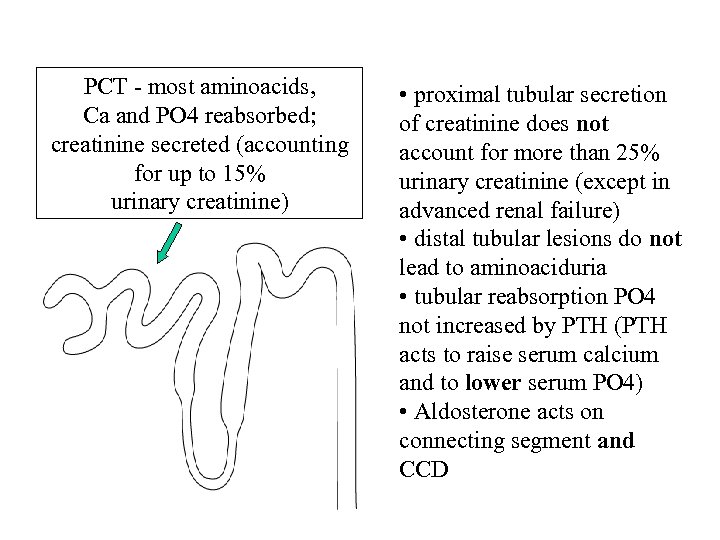

1. Which of the following is most accurate regarding tubular function? • A 90% of sodium has been reabsorbed by the start of the distal convoluted tubule • B Over 25% of urinary creatinine derives from proximal tubular secretion • C Aldosterone acts on collecting duct cells only • D Distal tubular lesions lead to amino aciduria • E Tubular reabsorption of phosphate can be increased by PTH

1. Which of the following is most accurate regarding tubular function? • A 90% of sodium has been reabsorbed by the start of the distal convoluted tubule • B Over 25% of urinary creatinine derives from proximal tubular secretion • C Aldosterone acts on collecting duct cells only • D Distal tubular lesions lead to amino aciduria • E Tubular reabsorption of phosphate can be increased by PTH

1. Which of the following is most accurate regarding tubular function? • A 90% of sodium has been reabsorbed by the start of the distal convoluted tubule • B Over 25% of urinary creatinine derives from proximal tubular secretion • C Aldosterone acts on collecting duct cells only • D Distal tubular lesions lead to amino aciduria • E Tubular reabsorption of phosphate can be increased by PTH

1. Which of the following is most accurate regarding tubular function? • A 90% of sodium has been reabsorbed by the start of the distal convoluted tubule • B Over 25% of urinary creatinine derives from proximal tubular secretion • C Aldosterone acts on collecting duct cells only • D Distal tubular lesions lead to amino aciduria • E Tubular reabsorption of phosphate can be increased by PTH

PCT - most aminoacids, Ca and PO 4 reabsorbed; creatinine secreted (accounting for up to 15% urinary creatinine) • proximal tubular secretion of creatinine does not account for more than 25% urinary creatinine (except in advanced renal failure) • distal tubular lesions do not lead to aminoaciduria • tubular reabsorption PO 4 not increased by PTH (PTH acts to raise serum calcium and to lower serum PO 4) • Aldosterone acts on connecting segment and CCD

PCT - most aminoacids, Ca and PO 4 reabsorbed; creatinine secreted (accounting for up to 15% urinary creatinine) • proximal tubular secretion of creatinine does not account for more than 25% urinary creatinine (except in advanced renal failure) • distal tubular lesions do not lead to aminoaciduria • tubular reabsorption PO 4 not increased by PTH (PTH acts to raise serum calcium and to lower serum PO 4) • Aldosterone acts on connecting segment and CCD